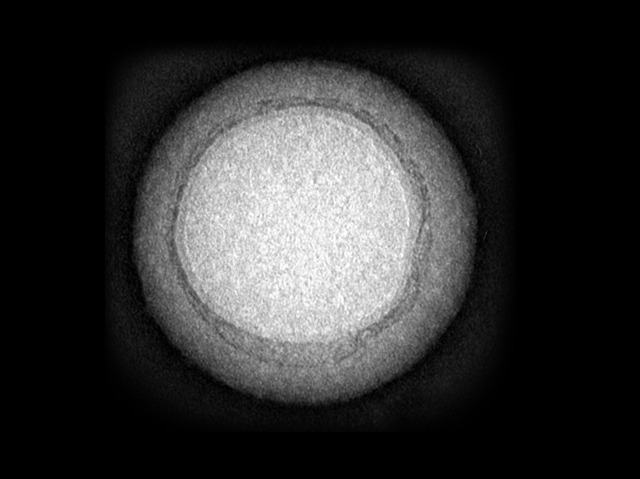

Diverting the enemy's firepower with a decoy is a favourite tactic of soldiers. So, when defending our body from toxic substances, the same strategy can work at a microscopic level. One such toxin infiltrates red blood cells (RBCs) – which are responsible for carrying oxygen around the body – causing them to become porous and die. A thin layer of RBC membrane (dark outer layer in image) wrapped around a synthetic core (light inner area) is attacked in much the same way, but without the damaging effects to the body. As shown in mice, these decoy nanosponges can keep the dangerous substance locked up and away from real RBCs until the liver can safely break it down. Nanosponges like these could provide treatment for a wide variety of chemical threats – from certain bacteria to scorpions and snakes – which all use similar toxins to target their prey.